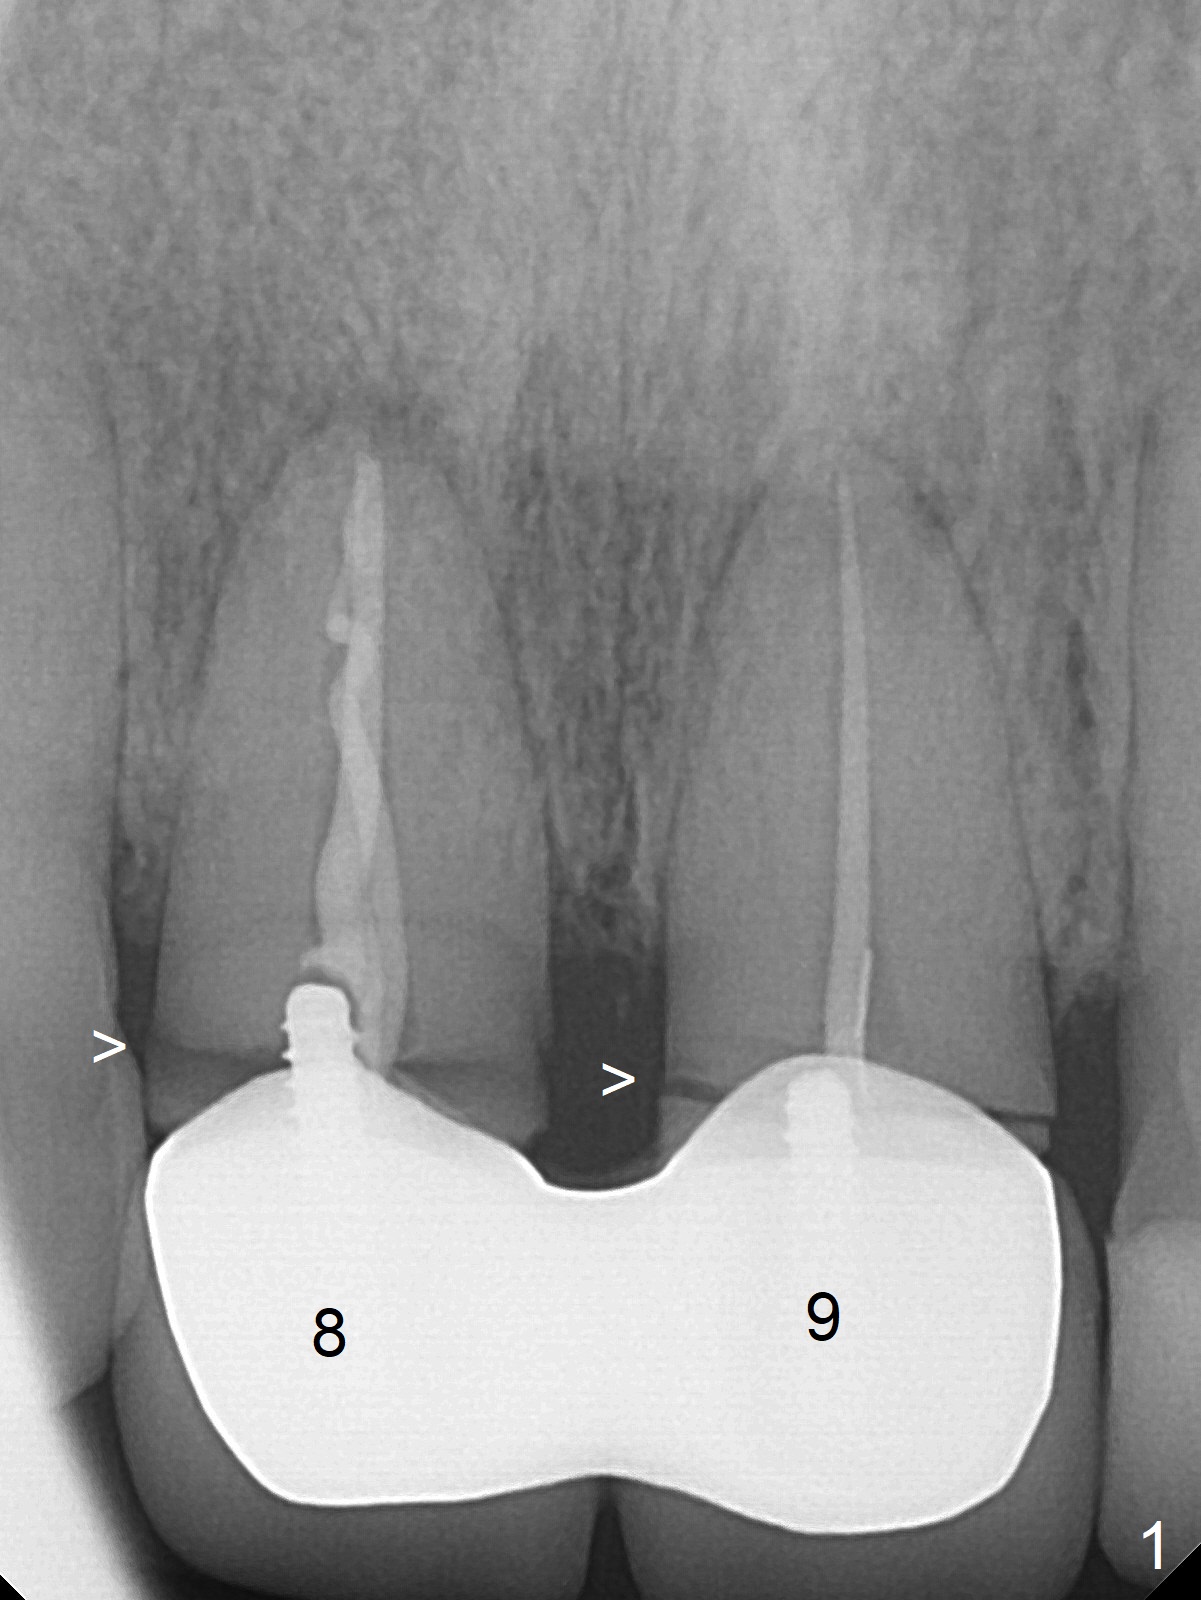

A 36-year-old woman fractures the teeth 8 and 9 while the implant at #3 is healing (Fig.1 arrowheads). It appears that the teeth are wide enough to accept 4.5x14 mm implants (Fig.2).